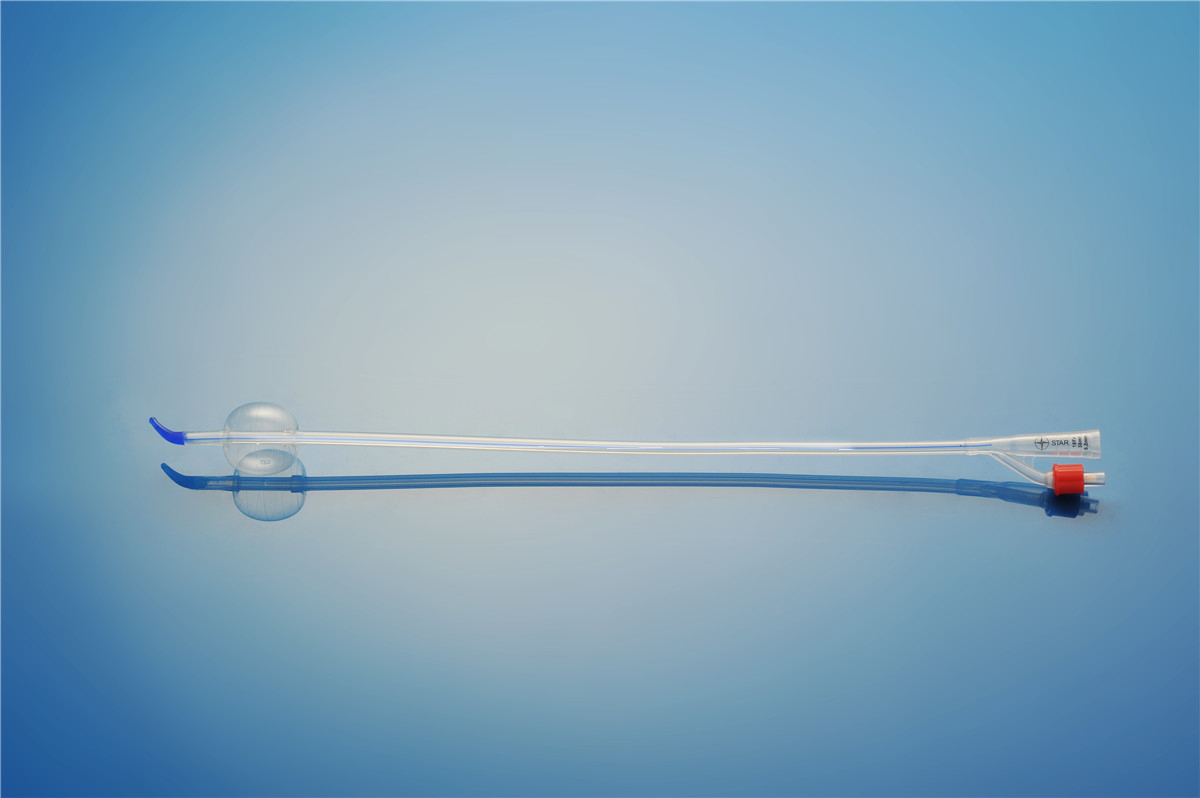

【產品名稱】一次性使用無菌導尿管(取樣型使用) 【型號】雙腔彎頭取樣型 【規格】:12FR-18FR 【主要結構����、性能】由膠乳為主要原材料制成,可配卡片���。

型號:雙腔氣囊彎頭型規格:雙腔氣囊彎頭型:12Fr(5-10mL)���、14Fr(5-10mL)����、16Fr(5-10mL)���、16Fr(30mL)�、18Fr(30mL)����;結構及組成/主要組成成分:產品由導尿管、水潤滑包(選配)組成。雙腔由球囊腔充起錐形接口�、排液腔錐形接口、閥門����、管身、球囊�、排液孔組成(尖端有普通尖頭和彎頭區...